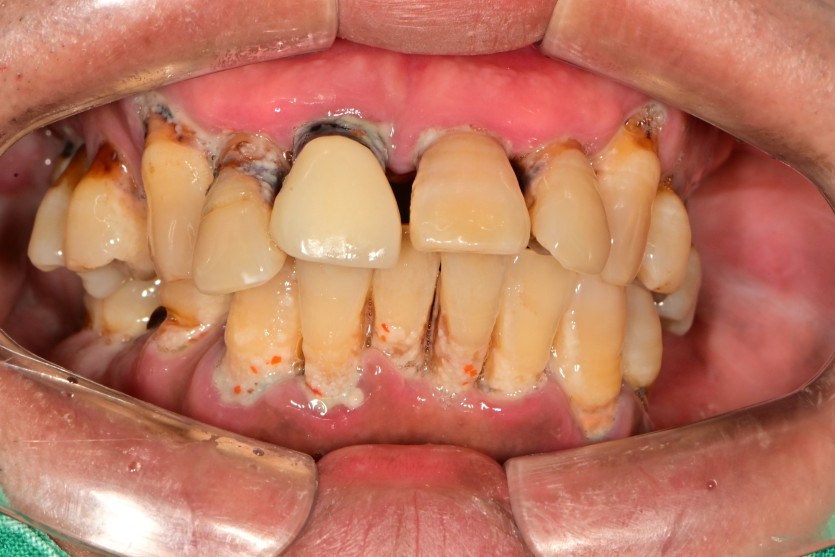

만 53세 전체 임플란트

전체 임플란트 증례입니다.

18개의 임플란트로 완성하였습니다.